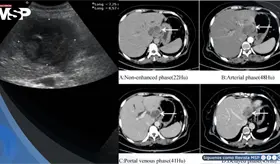

Lo que comenzó como un cuadro frecuente de dolor pélvico y dismenorrea en una mujer, terminó siendo un carcinoma folicular originado en estruma ovárico maligno. La paciente tenía solo 35 años, marcadores tumorales completamente normales y ninguna alteración tiroidea.